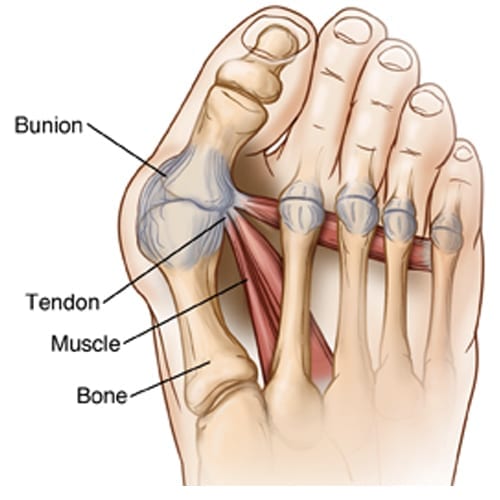

무지외반증이란 엄지발가락의 변형과 그로 인한 관절의 통증을 일컫는 질환이에요. 무지, 즉 엄지발가락이 새끼발가락 쪽으로 휘면 발 안쪽이 돌출되고 그 부위가 계속해서 신발과 닿게 되면 염증이 생기고 통증이 유발되어요.

무지외반증 수술은 엄지발가락이 돌출됨에 따라 타이트해진 엄지발가락 바깥쪽을 늘려주고 반대로 늘어난 엄지발가락 안쪽을 타이트하게 잡아주어 발가락의 본래 모양을 되찾아줘요. 또한 발등 뼈를 평행 이동시켜 발 폭을 줄여주고요.